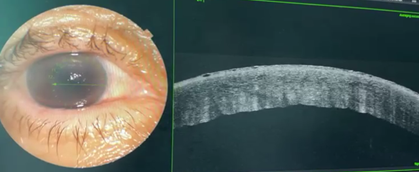

Medical therapy was continued, with gradual tapering of corticosteroid drops (reduced by one instillation per week). At 6 weeks, follow-up revealed spectacular improvement, with complete corneal clearing (Figure 5) and visual acuity of 8/10.

No surgical intervention was required, suggesting spontaneous regeneration and functional recovery of Descemet’s membrane.

Figure 5: Slit-lamp image at 6 weeks showing a clear cornea with significant improvement compared to previous findings.